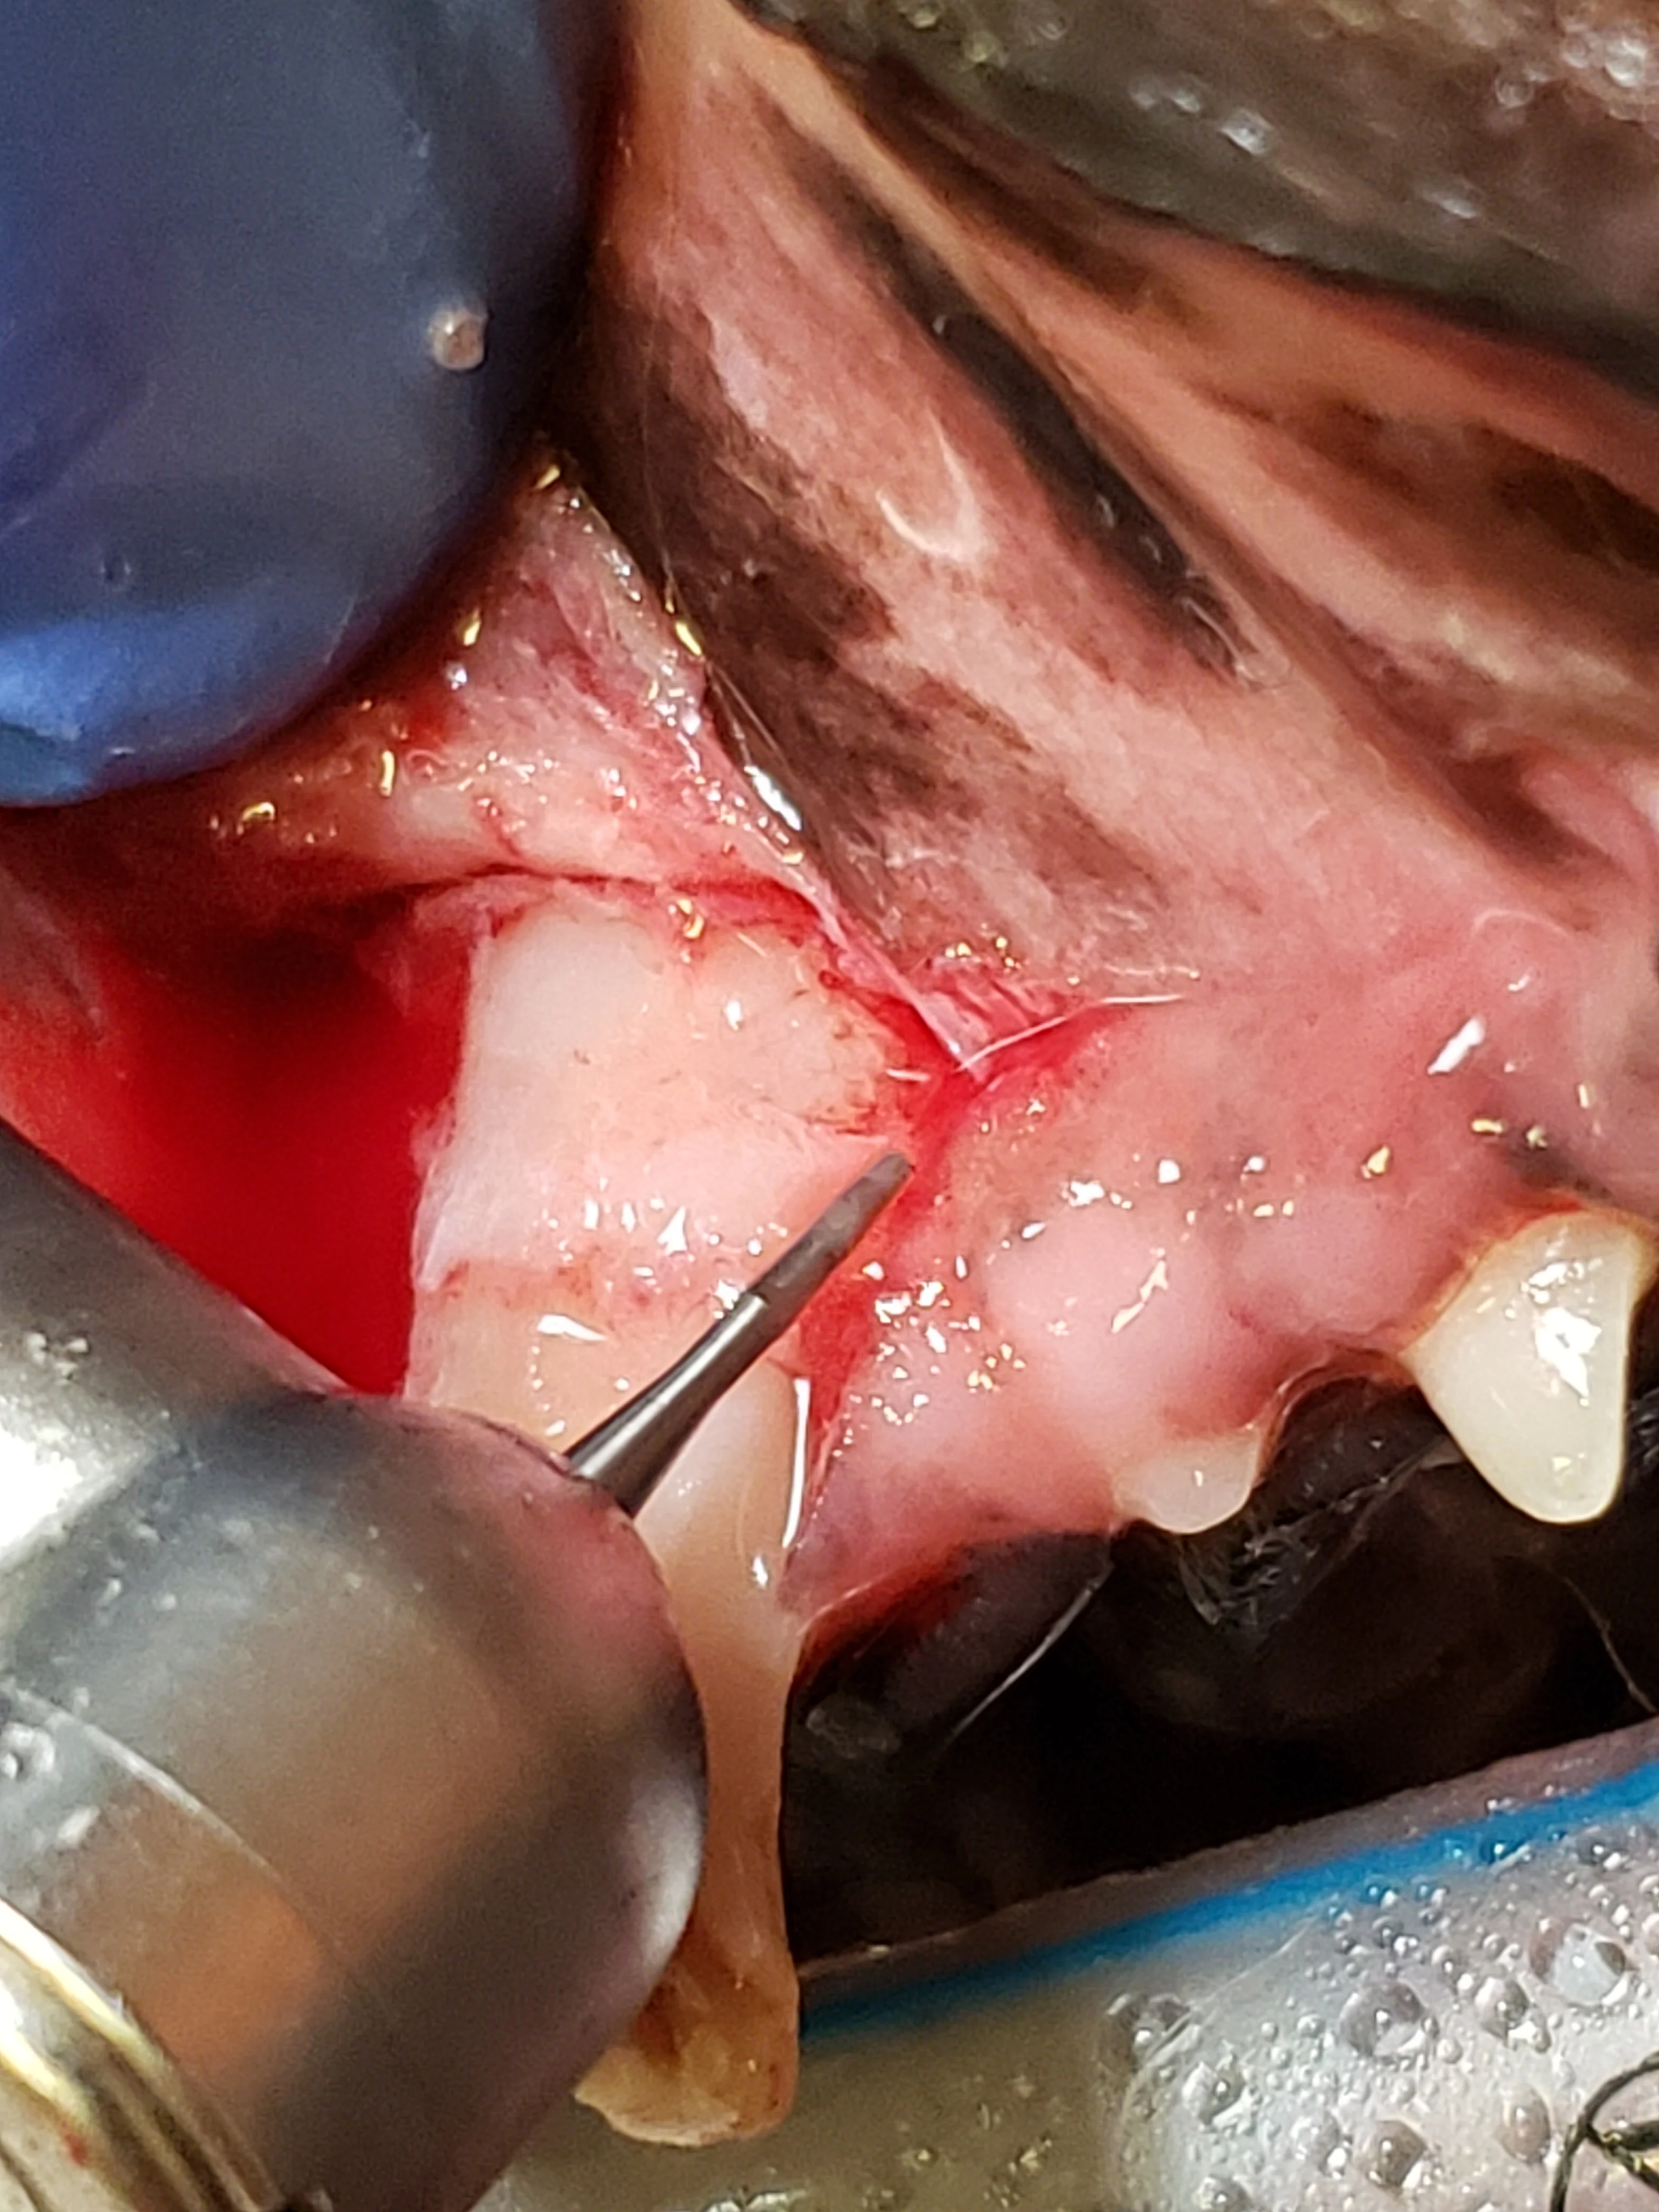

Step 9: Elevate the Palatal Mucosa

Use a periosteal elevator to elevate the palatal mucosa and the attached gingival edges at the releasing-incision sites 1 to 2 mm from the alveolar bone. Freshen any intact epithelial edges with scissors.

Step 10: Perform Alveoloplasty

Use a bur (preferably diamond) to remove rough or diseased bone in the alveolus to provide a smooth surface. Use hand curettes or serrated periosteal elevators to debride granulation tissue or diseased soft tissue adjacent to or in the alveolus.

Step 11: Suture the Extraction Site

Confirm the flap is released enough to be placed over the extraction site without tension (A). If not done previously, incise a thin layer of periosteum on the underside of the flap (see Step 4). Close the mucogingival flap over the extraction site using absorbable suture (B). Use simple interrupted sutures to anchor the flap to the mesial and distal aspects and simple interrupted, cruciate, or continuous sutures to close the remaining edges (C; lines indicate where additional sutures should be placed).